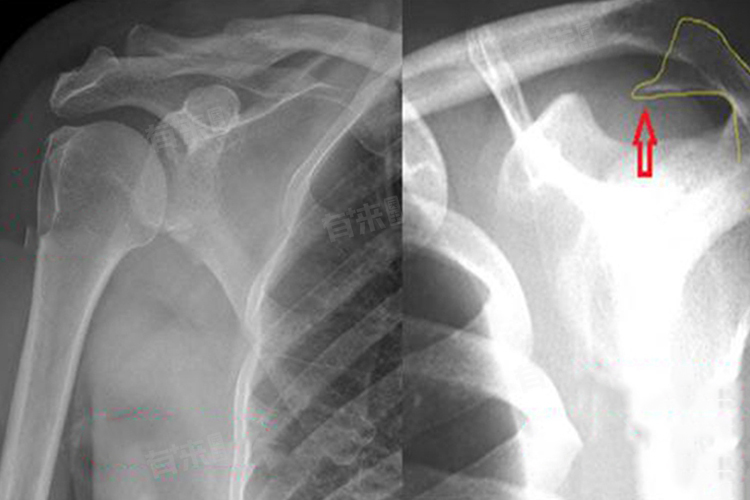

- 开放性手术:在关节严重受损,如关节面严重破坏、骨关节炎晚期等情况下,可能需要进行开放性手术,如肩关节置换术。这种手术可以重建肩关节功能,缓解疼痛,但手术风险和术后恢复时间相对较长。在决定手术治疗前,需要综合评估患者的病情、身体状况和手术风险等因素。